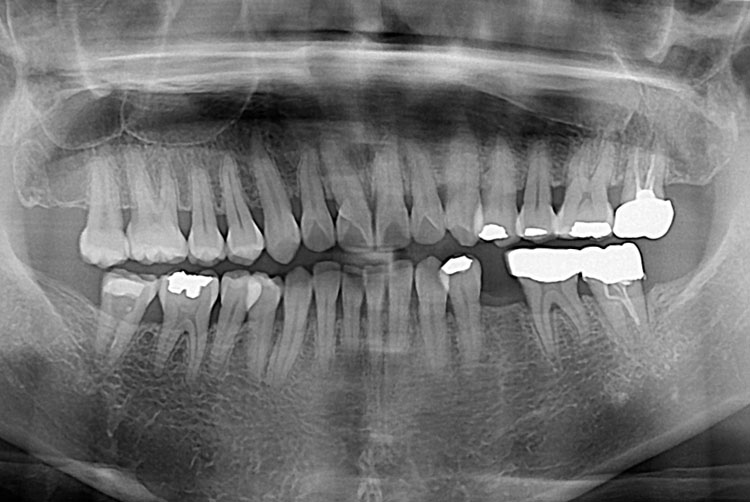

치료전 : 2019-10-31